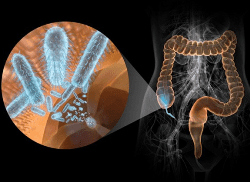

Острая кишечная инфекция

Кишечные инфекции – одно из самых распространенных заболеваний в мире. Распространенность их среди населения чрезвычайно высокая, как в детской возрастной группе, так и у взрослых. Когда мы говорим о кишечной инфекции, то подразумеваем острое кишечное заболевание...